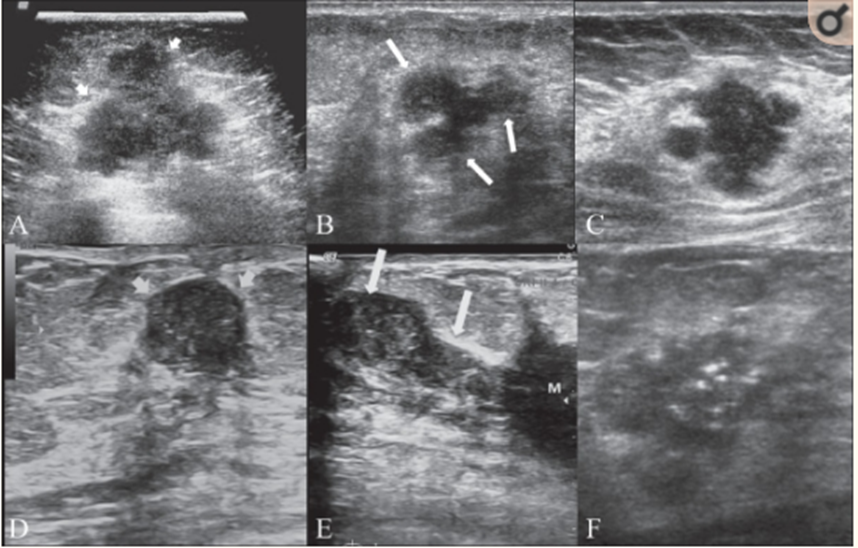

Khối ung thư vú trên siêu âm

3.2 Siêu âm tuyến vú

Siêu âm vú là phương pháp chẩn đoán hình ảnh ung thư vú bằng cách xây dựng và tái tạo hình ảnh về cấu trúc bên trong tuyến vú và cơ thể. Siêu âm vú cũng hỗ trợ hướng dẫn mũi kim trong các thủ thuật xâm lấn như: Chọc hút nang, chọc hút sinh thiết, hướng dẫn kim sinh thiết có lõi,... Phương pháp này đang được áp dụng khá phổ biến vì chi phí thấp, dễ thực hiện, không đau và không gây hại cho bệnh nhân. Siêu âm chẩn đoán bệnh lý tuyến vú có độ chính xác cao, có thể chẩn đoán được những tổn thương nhỏ có đường kính dưới 5mm, có giá trị trong phát hiện ung thư vú sớm.